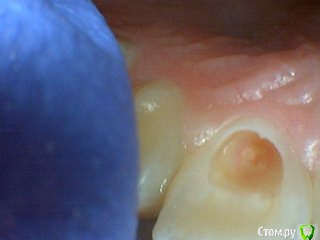

Давлетшин Опубликовано 13 июля, 2017 Поделиться Опубликовано 13 июля, 2017 Обидно понимаешь за детство, сообщений особо нет. подумать не над чем.два клинических случая. будут там пульпиты или нет? вот в чем вопрос. в одном случае пломба Витример в другом Эстелайт, без прокладок. Порядок фото несколько нарушен. Работаем над этим. Ссылка на комментарий

Давлетшин Опубликовано 13 июля, 2017 Автор Поделиться Опубликовано 13 июля, 2017 второй случай. один пациент 1 1 Ссылка на комментарий